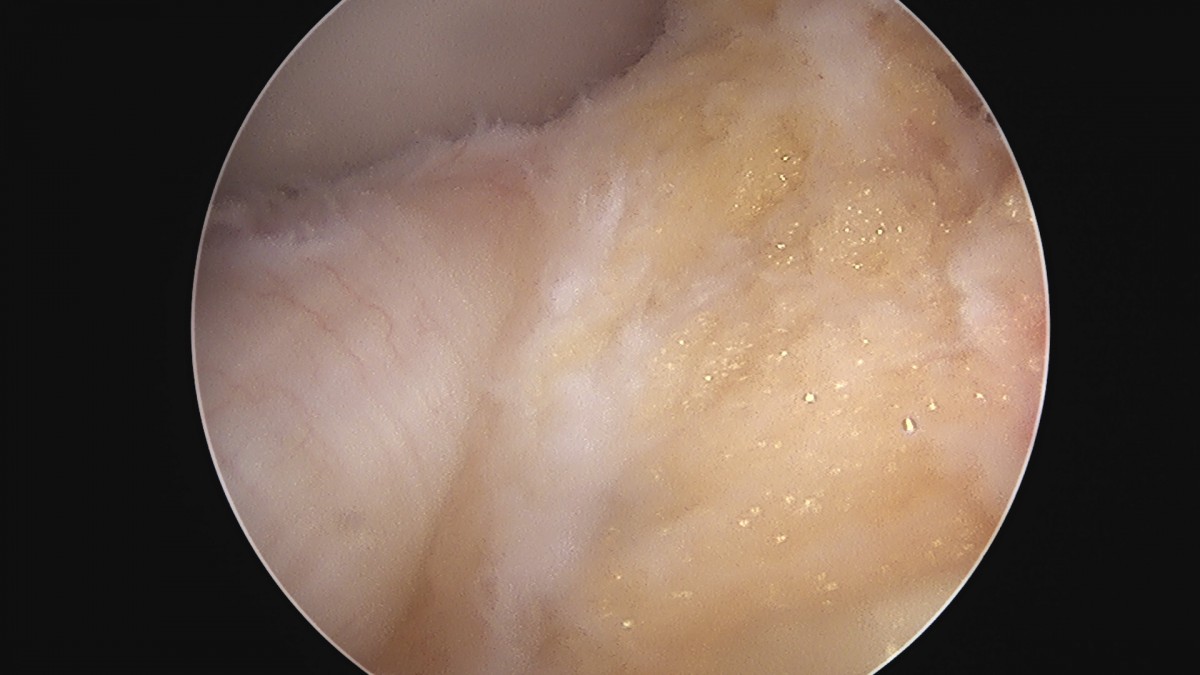

이재상원장님 무릎 반월상 연골판 절제술 김건O 환자

dae765e4d9ac96aee867c9d6292d8784_1758006493_453.jpg

dae765e4d9ac96aee867c9d6292d8784_1758006494_0555.jpg

dae765e4d9ac96aee867c9d6292d8784_1758006494_6445.jpg

dae765e4d9ac96aee867c9d6292d8784_1758006495_2691.jpg

dae765e4d9ac96aee867c9d6292d8784_1758006495_851.jpg

dae765e4d9ac96aee867c9d6292d8784_1758006496_4269.jpg

dae765e4d9ac96aee867c9d6292d8784_1758006497_0031.jpg

dae765e4d9ac96aee867c9d6292d8784_1758006497_5791.jpg

dae765e4d9ac96aee867c9d6292d8784_1758006498_1777.jpg

dae765e4d9ac96aee867c9d6292d8784_1758006498_7597.jpg